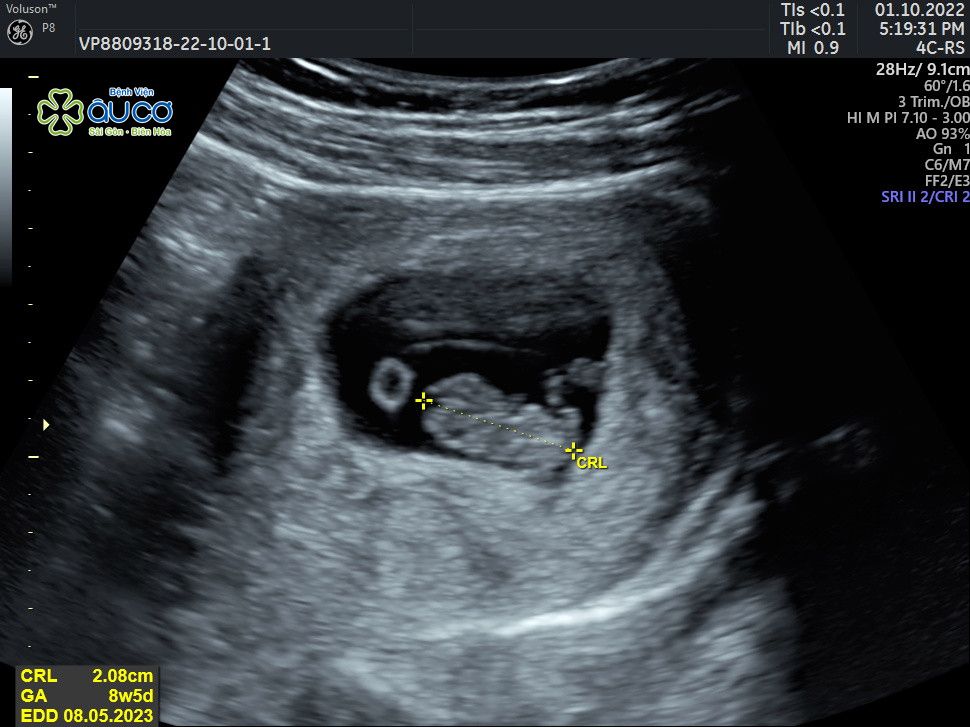

* Những hình ảnh siêu âm đáng yêu nhưng không kém phần nghịch ngợm của con qua các mốc thời gian:

| 8 tuần 5 ngày |

![]() |